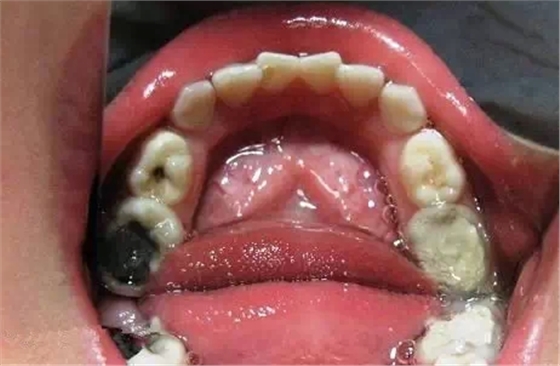

我認(rèn)為目前兒童牙科診療存在的困難如下: 乳牙根尖周病是指根尖周圍或根分叉部位的牙骨質(zhì)、牙周膜和牙槽骨等組織的炎癥性疾病,其病因和臨床表現(xiàn)均有其特點(diǎn)。(引自醫(yī)科大 課件) 乳牙牙髓壞死的診斷很重要! 乳牙急性根尖周炎的應(yīng)急處理,首先應(yīng)建立髓腔引流,用快速鋒利的渦輪機(jī)牙鉆開(kāi)髓,開(kāi)放髓腔,使炎性滲出物或膿液通過(guò)根管引流。 (福建醫(yī)大口腔醫(yī)院 高生輝老師的圖片) 已形成粘膜下膿腫的還需在口腔內(nèi)的腫脹部位做局部切開(kāi)排膿,而腫脹嚴(yán)重者,則需用碘仿紗條進(jìn)行引流。(醫(yī)大口腔醫(yī)院 高生輝老師圖片) 重點(diǎn)介紹乳牙的根管治療! 治療步驟:1)去齲、開(kāi)髓 揭髓室頂 2)根管預(yù)備 根管沖洗 3)封藥 4)根充,乳牙根充須用能吸收的糊劑。然后進(jìn)行常規(guī)充填或冠修復(fù) (以上圖片引用自福建醫(yī)大附屬口腔醫(yī)院兒童科 高生輝老師的課件,非常感謝?。? 我的根充糊劑的 自制Vitapex 氫氧化鈣7g碘仿9g二甲基硅油10ml 要點(diǎn):氫氧化鈣、碘仿要在研缽內(nèi)研細(xì),硅油量可根據(jù)個(gè)人的習(xí)慣調(diào)整糊劑的粘稠度,昏勻后裝至1ml注射器或瓶?jī)?nèi)。 經(jīng)856例臨床驗(yàn)證與原裝Vitapex無(wú)差異。 成本:10ml 15元,配制所需時(shí)間10分鐘 氫氧化鈣500g/14元,碘仿20g/20元,二甲基硅油500ml/34元 Vitapex-成 份 氫氧化鈣 30% 刺激“母”細(xì)胞,有助根管尖端化。高酸堿值可中和厭氧菌產(chǎn)生的毒素。 三碘甲烷 40.4% 抗菌,可增加放射性非通透性。 聚硅脂油 22.4% 潤(rùn)滑劑,可保證牙根管壁的包被良好。不會(huì)硬化且保證可溶性的氫氧化鈣在牙根管中持續(xù)發(fā)揮作用。 填充物 6.9% 1,主方:純氧化鋅慢干粉+丁香酚+少許碘仿(這書(shū)上有的)